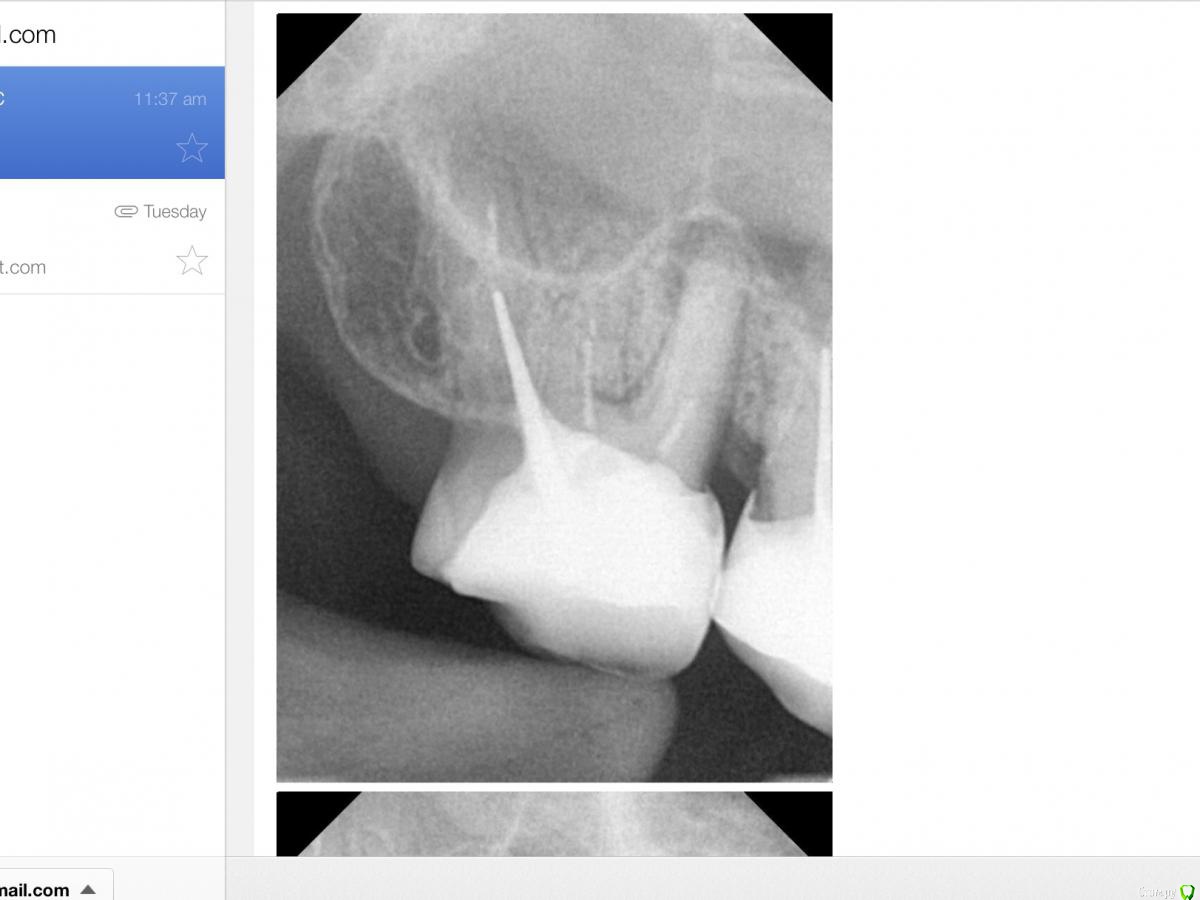

RUVIK Опубликовано 21 декабря, 2018 Автор Поделиться Опубликовано 21 декабря, 2018 Вот прицельные снимки под микроскопом .Что скажите ,стоит ли пробовать перелечивать каналы или шансов нет? Ссылка на комментарий

RUVIK Опубликовано 21 декабря, 2018 Автор Поделиться Опубликовано 21 декабря, 2018 (изменено) Вот прицельные снимки под микроскопом .Что скажите ,стоит ли пробовать перелечивать каналы или шансов нет? Изменено 21 декабря, 2018 пользователем RUVIK Ссылка на комментарий